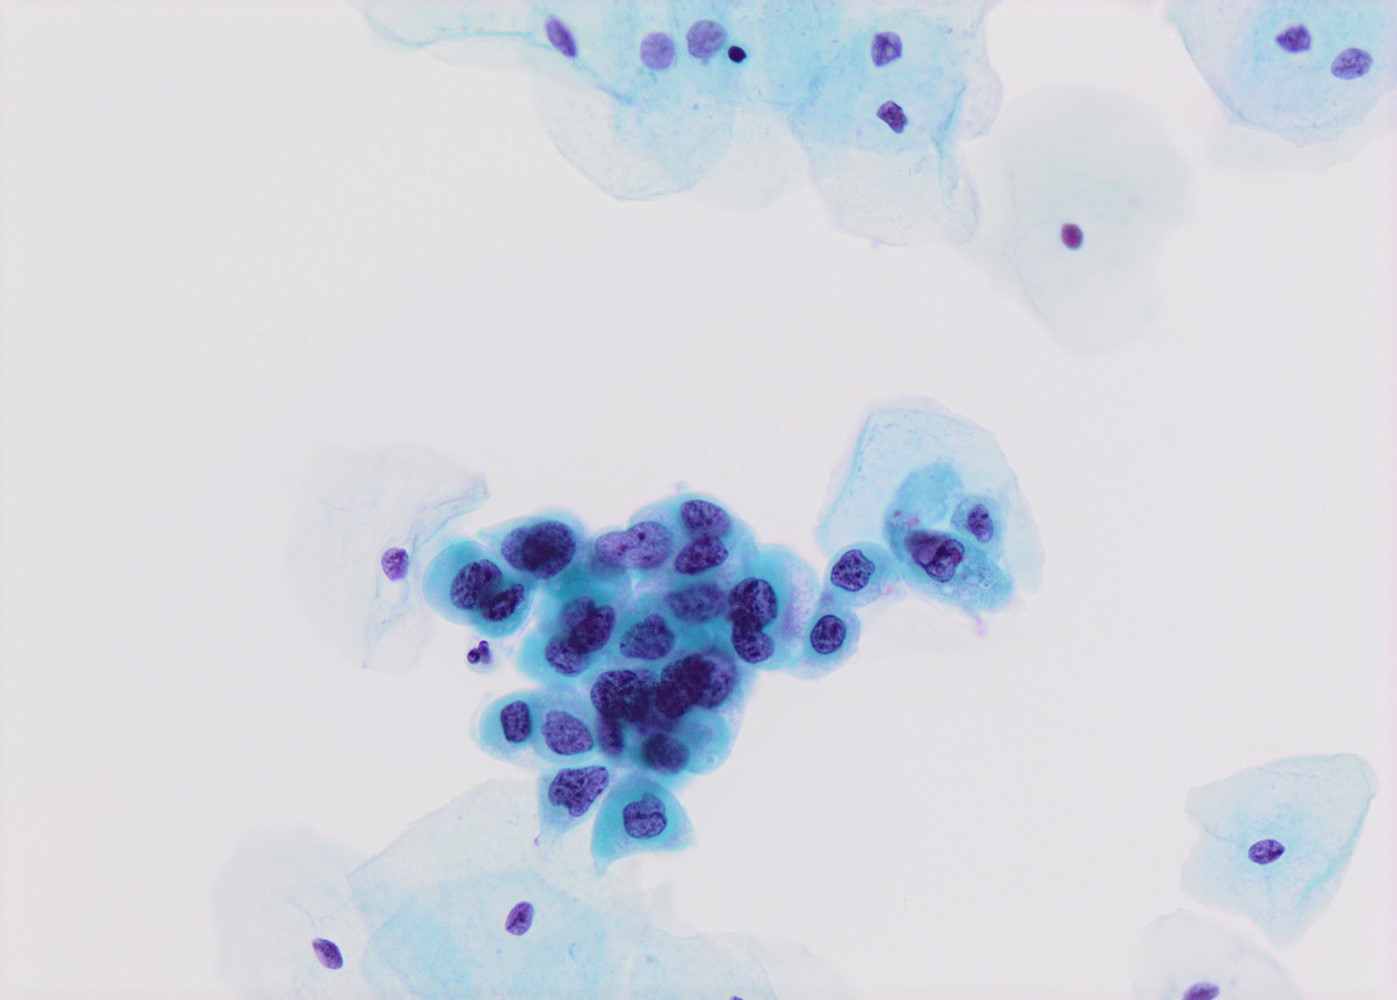

- High nuclear to cytoplasmic (N/C) ratio, nuclear enlargement (usually threefold), hyperchromasia, coarse chromatin, nuclear membrane irregularities and inconspicuous nucleoli

- Arranged as syncytium / hyperchromatic crowded groups or single cells

- Additional information available at: HSIL cytology

- References: Nucci: Gynecologic Pathology - A Volume in Foundations in Diagnostic Pathology Series, 2nd Edition, 2020

Cytology images